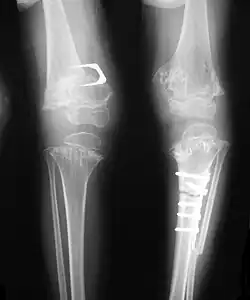

Skeletal radiography

Accurate assessment of plain radiographic findings remains an important contributor to diagnosis of pseudoachondroplasia. It is noteworthy that vertebral radiographic abnormalities tend to resolve over time. Epiphyseal abnormalities tend to run a progressive course. Patients usually suffer early-onset arthritis of hips and knees. Many unique skeletal radiographic abnormalities of patients with pseudoachondroplasia have been reported in the literature.[2][7][4]

- Together with rhizomelic limb shortening, the presence of epiphyseal-metaphyseal changes of the long bones is a distinctive radiologic feature of pseudoachondroplasia.

- Dysplastic/hypoplastic epiphyses especially of shoulders and around the knees.

- Metaphyseal broadening, irregularity and metaphyseal line of ossification. These abnormalities that are typically encountered in proximal humerus and around the knees are collectively known as "rachitic-like changes".

- Radiographic lesions of the appendicular skeleton are typically bilateral and symmetric.